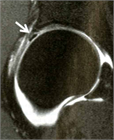

1. 単純X線撮影と読影のポイントを追加し、大腿骨寛骨臼インピンジメント(FAI)の疫学・関節症性変化への進行に関する最新の文献を参考に加筆した。